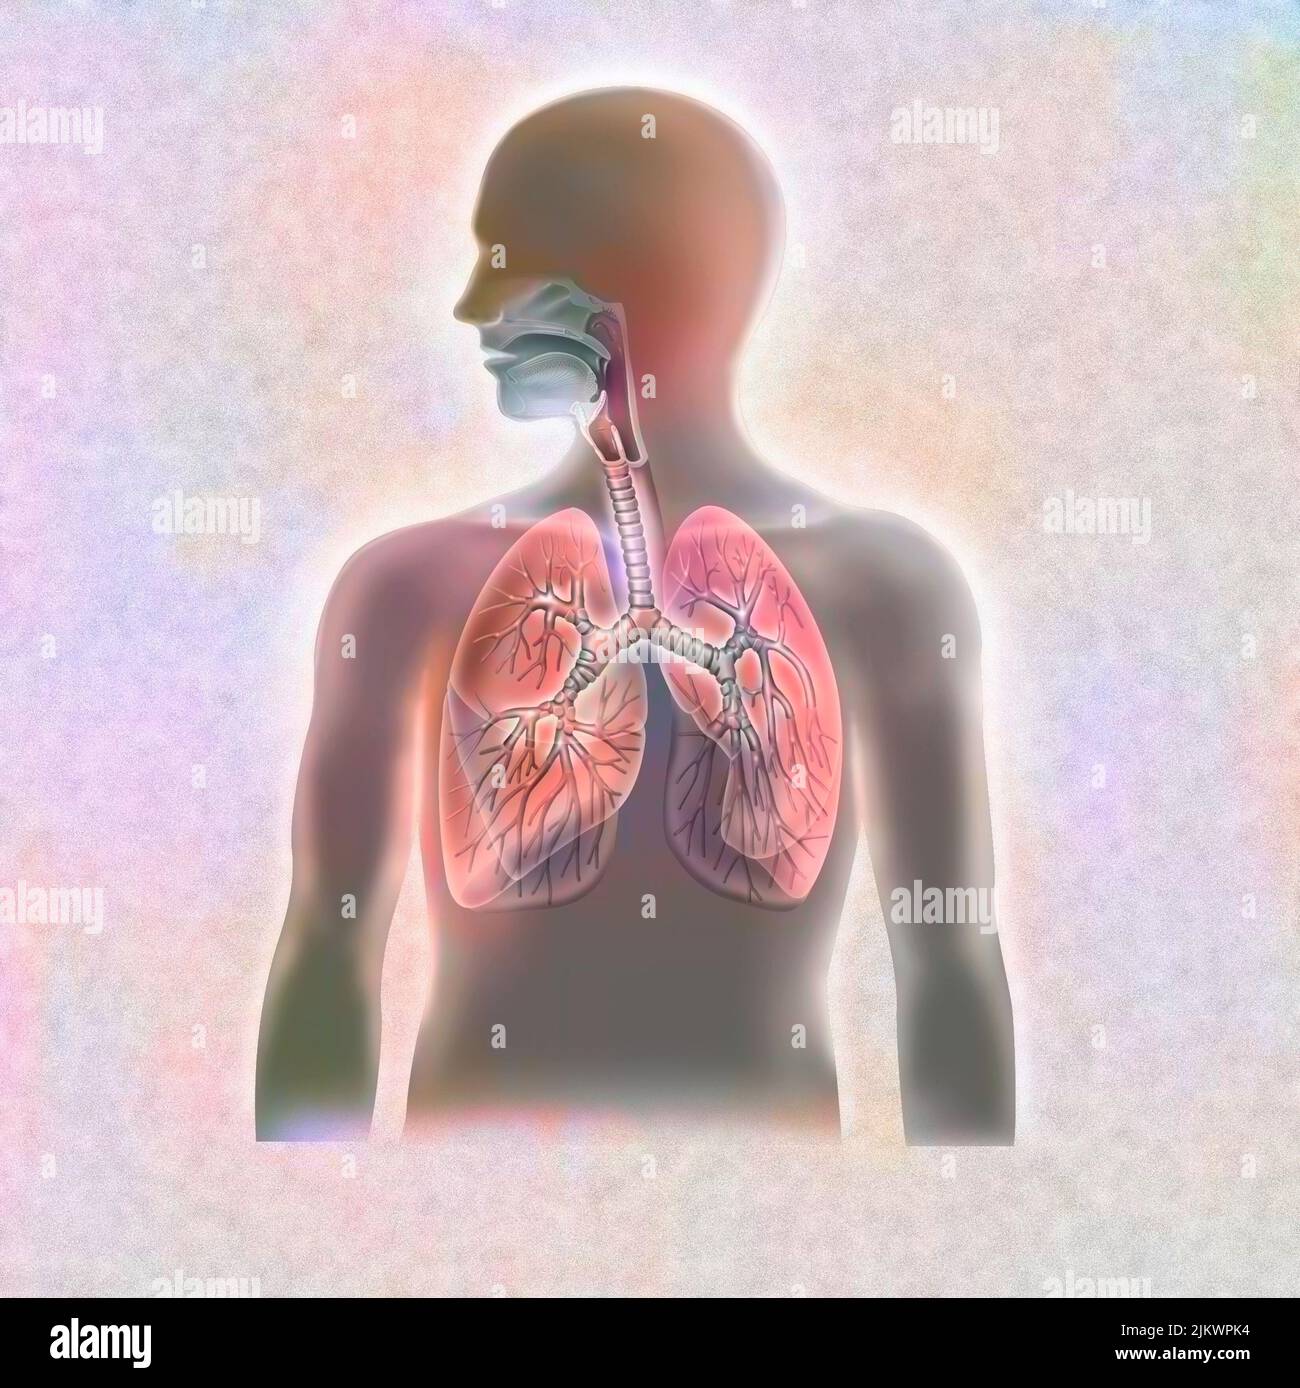

RFHT54Y0–Männliche Anatomie. Skelett und hervorgehobenen Lungen. 3D Illustration. Clipping-Pfad enthält.